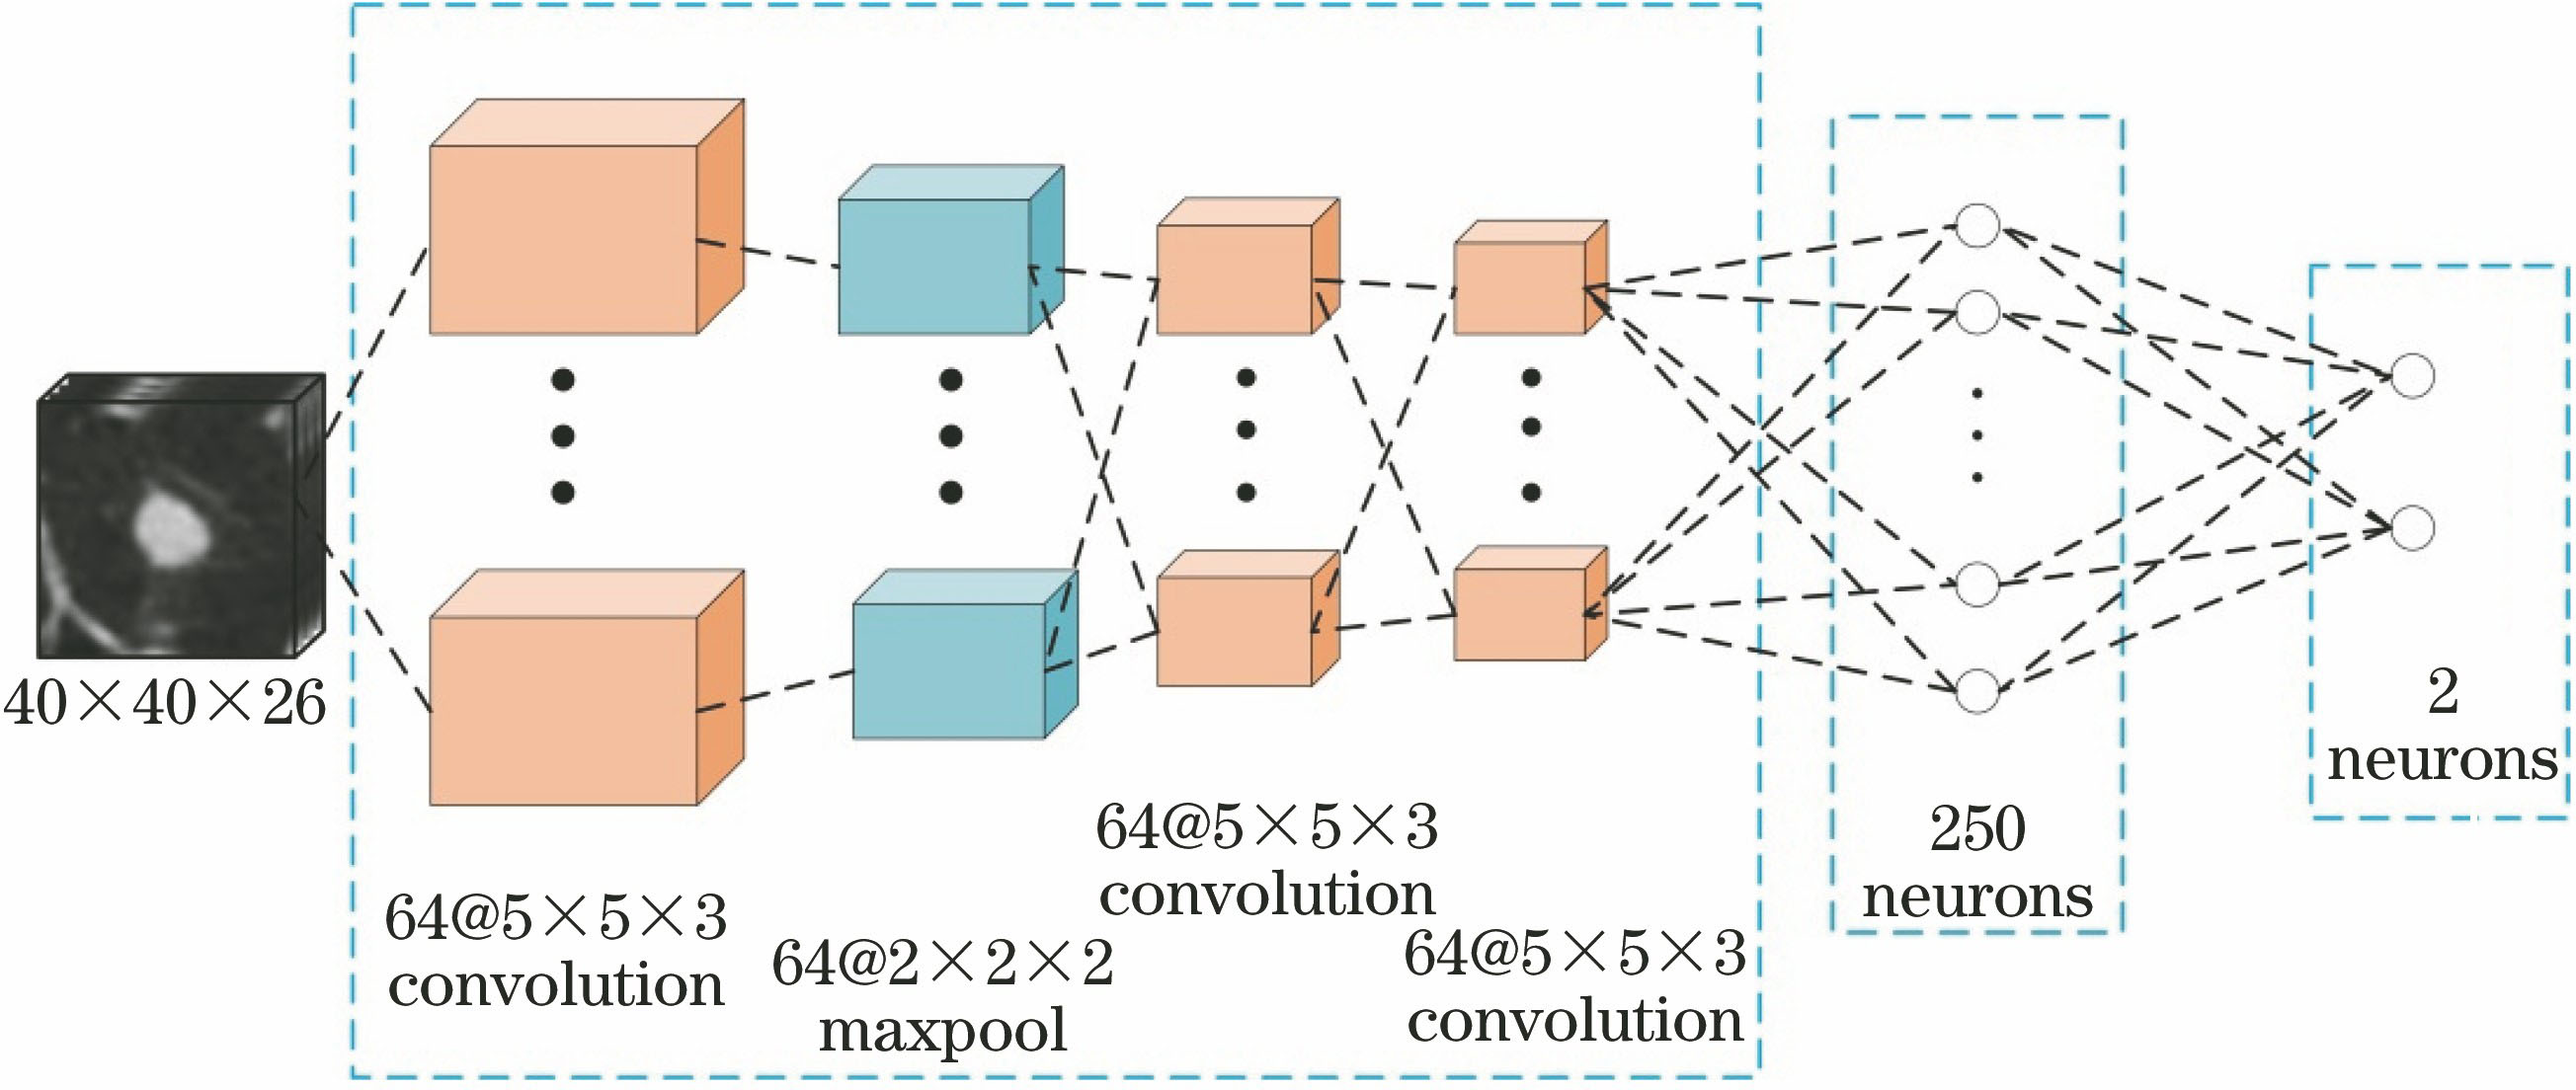

图 3. 3D卷积神经网络假阳性去除系统网络的结构

Fig. 3. Structure of 3D convolution neural network false positive removal system network